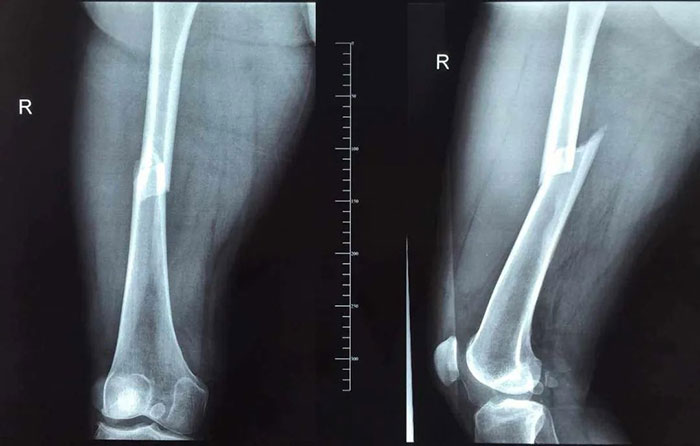

傳統(tǒng)手術后效果

手術當天,在麻醉科的配合下,創(chuàng)傷骨三科(骨九科)團隊通過C型臂透視下微創(chuàng)復位骨折,并打入大腿髓內針進行固定,只用幾個小口就完成了手術,整個手術過程出血很少,完全不需要輸血,手術順利,骨折復位良好。

微創(chuàng)手術后效果